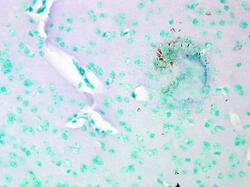

LS-C231564 IHC

Method: